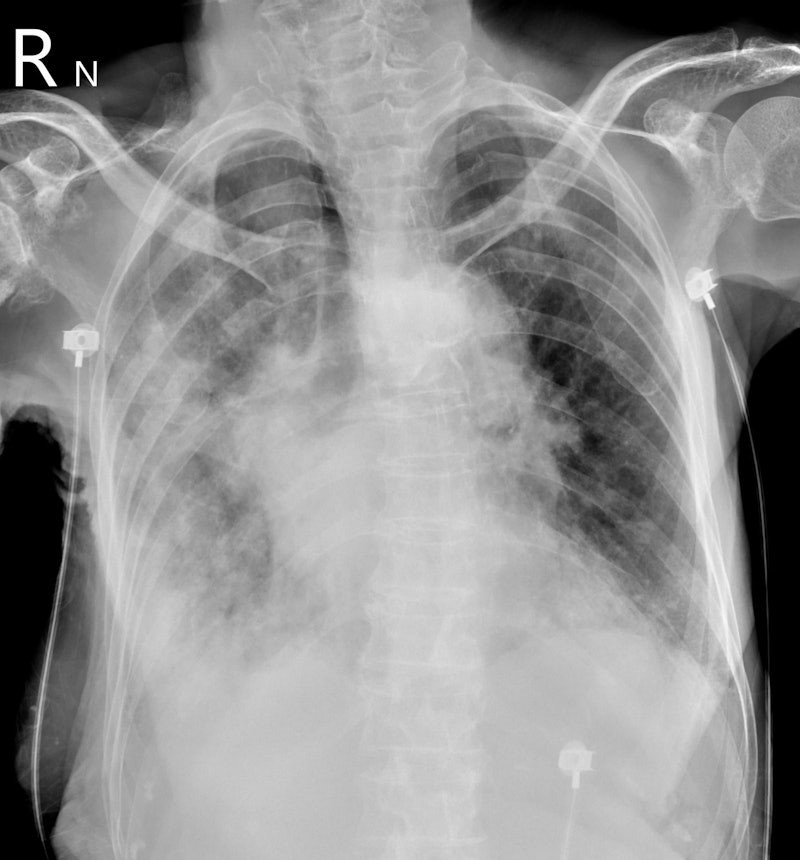

Bên cạnh đó, nhiều thông tin cho biết, khi tình trạng của Từ Hy Viên trở nặng, kết quả chụp CT cho thấy cả hai lá phổi của Từ Hy Viên đã trắng xóa. Không lâu sau, cô trút hơi thở cuối cùng.

Ngày 5/2, bác sĩ Tô Nhất Phong, chuyên khoa lồng ngực tại chi nhánh Dương Minh của Bệnh viện Thống nhất thành phố Đài Bắc (Đài Loan, Trung Quốc), giải thích rõ hơn về tình trạng "lá phổi trắng" của nữ diễn viên xấu số. Theo bác sĩ này, "phổi trắng xóa" thực chất phản ánh tình trạng viêm phổi nặng dẫn đến khó thở.

Khi viêm phổi nặng xảy ra, phế nang sẽ chứa đầy đờm và nước bị viêm. Khi phế nang phủ đầy đờm và nước, không khí không thể vào. Do đó, theo bác sĩ họ Tô, phổi trắng thực chất là "bệnh nhân bị chính đờm của mình nhấn chìm".

Bác sĩ Tô nói thêm, khi phổi trắng xuất hiện, bệnh nhân thở mạnh nhưng phổi mất khả năng trao đổi khí, oxy trong máu tiếp tục giảm. Khi độ bão hòa oxy trong máu giảm xuống dưới 89%, đó là tình trạng thiếu oxy. Nếu không được điều trị, bệnh nhân có thể tử vong trong vòng nửa ngày hoặc vài giờ do ngừng tim và ngừng hô hấp.